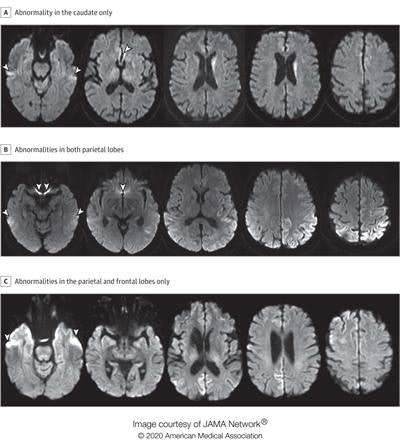

Diffusion MRI has long been used to diagnose prion diseases, with a basic protocol that includes identifying abnormal signals in the caudate and putamen, the researchers noted. In recent years, evaluation criteria for diffusion MRI for prion disease diagnosis were expanded to include signal intensities in the cortex of at least two brain lobes (with the exception of the frontal lobes on diffusion-weighted MRI and fluid-attenuated inversion recovery, or FLAIR); these updated criteria have now become the current standard.

"These criteria might be too conservative, missing the diagnosis of patients with frontal cortex and/or only one lobe involvement or with only the caudate or putamen affected," the team cautioned.

Bizzi's group sought to evaluate the sensitivity and specificity of diffusion MRI for diagnosis of Creutzfeldt-Jakob disease with an index text that includes the new criterion of at least one positive brain region among the cortex of the frontal, parietal, temporal, and occipital lobes; the caudate; the putamen; and the thalamus. The investigators compared this new index test performance with current criteria, as well as with the performance of cerebrospinal fluid tests.